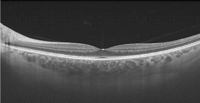

En la

Figura 2 se muestra un paciente con síndrome de Usher: en el recuadro verde (imagen superior derecha), la fóvea presenta una anatomía conservada, pero inmediatamente fuera de ella, en el recuadro rojo, se observa una pérdida de la anatomía normal a expensas de las cuatro capas externas, con atrofia del EPR. En la parte inferior de la composición se ofrece una imagen completa de la DRI-OCT.

Figura 2. DRI-OCT patológica. Paciente con síndrome de Usher. Imagen superior izquierda: retinografía de fondo de ojo del paciente. Imagen superior derecha: DRI-OCT foveal; en el recuadro verde, ampliación de la fóvea, con anatomía conservada; inmediatamente fuera de ella, en el recuadro rojo, pérdida de la anatomía normal a expensas de las cuatro capas externas con atrofia del EPR. Imagen inferior de la composición: DRI-OCT completa en la que se ven tanto el nervio óptico como la mácula.

Fijándose en el espesor de la coroides en la imagen de DRI-OCT de este paciente (

Figura 2, imagen inferior) y comparándola con la siguiente imagen de un voluntario sano (

Figura 3), puede observarse una disminución en el espesor.

Figura 3. DRI-OCT macular en voluntario sano: puede observarse un mayor espesor de la coroides comparando con la DRI-OCT del paciente con distrofia retiniana de la Figura 2.